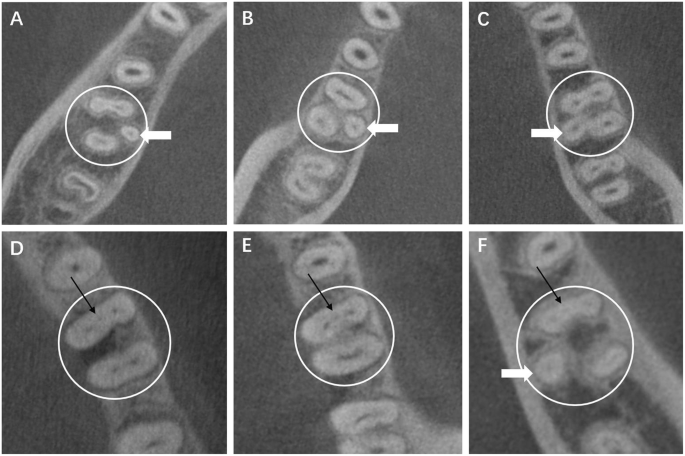

Cases of mandibular first molars with RE or MMC in the axial section are showed in Fig. 1. The detection rates of the MMC and RE were 3.41 and 25.04%, respectively, as calculated by individuals, and 1.79 and 22.15%, respectively, as calculated by the total teeth. The mean distances between the MMC and MBC orifice and between the MMC and MLC orifice were 1.84 mm and 1.95 mm, respectively, while the mean distances between the RE canal orifice and distobuccal canal orifice and between the RE canal orifice and mesiolingual canal orifice were 4.22 mm and 4.01 mm, respectively.

Cases of mandibular first molars with RE or MMC in the axial section; the white circles indicate the examined tooth; the white arrows indicate REs; the black arrows indicate MMCs. CBCT images show (A-C) mandibular first molars with RE, (D-E) mandibular first molars with MMC, (F) mandibular first molars with both RE and MMC